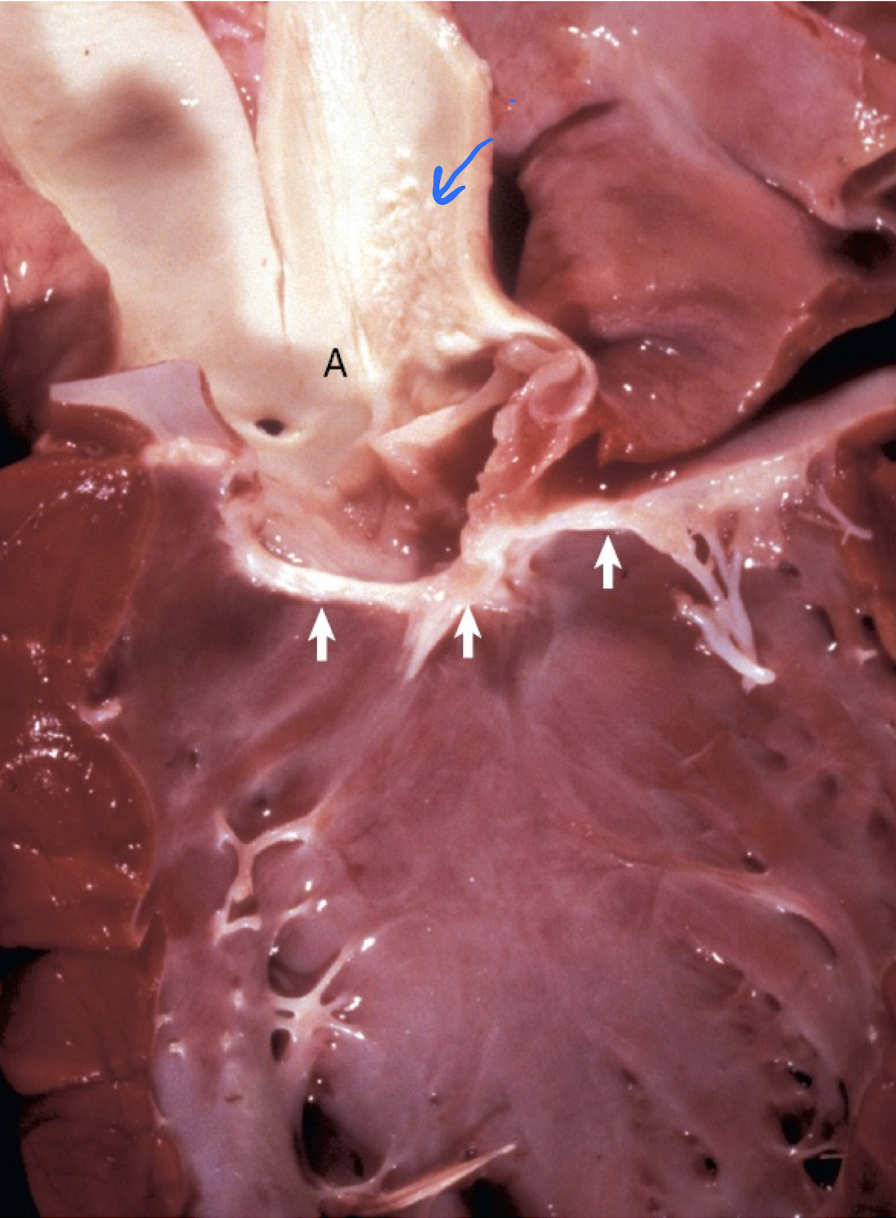

ID + sequela

A

VSD

- left-sided heart failure (LV to RV/directly into pulmonary trunk –> pulmonary edema)